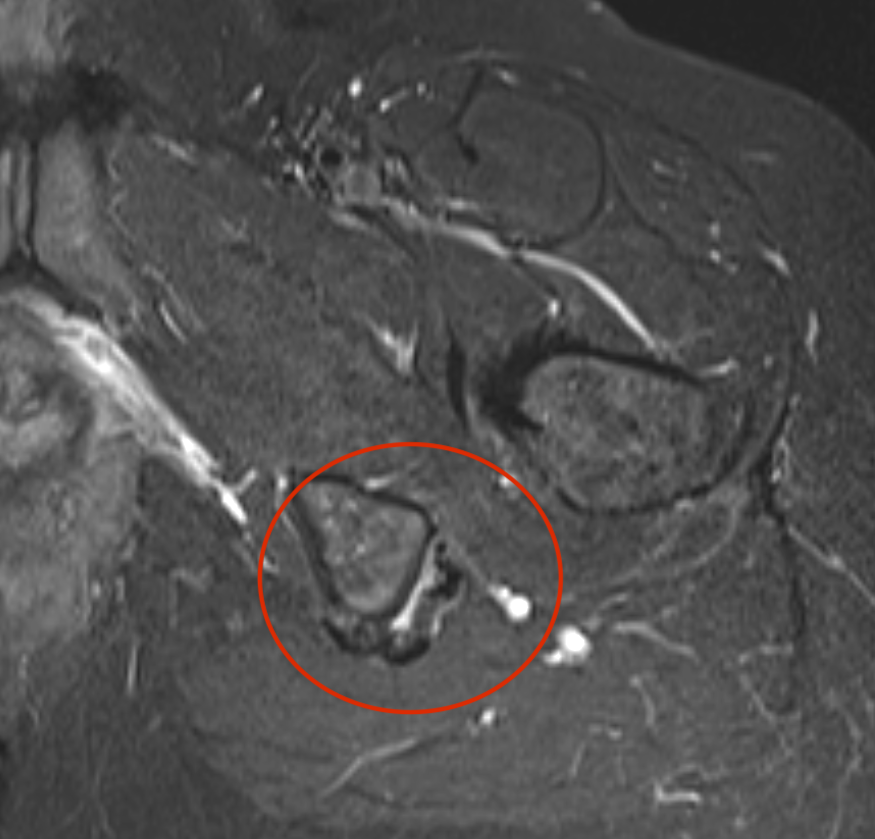

MRI

Complete / retracted tears

Proximal hamstring tear on right (red circle), normal insertion on tuberosity on left (blue circle)

Proximal hamstring avulsion on right - red circle is retracted hamstring tendon, blue circle is normal insertion on left

Proximal hamstring tear on right (red circle), normal insertion on left (blue circle)